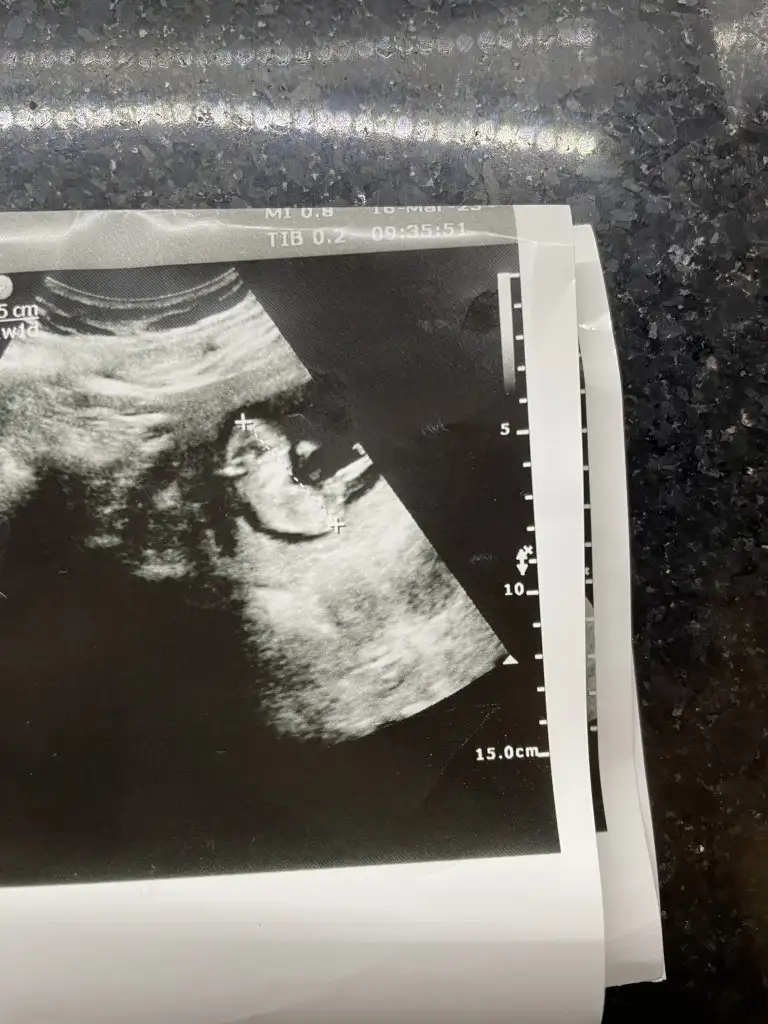

Merhabalar, benimde ultrason görüntülerime göre yorum yapabilecek var mı? ☺️ Şimdiden teşekkürler 🤲

Eklentiler